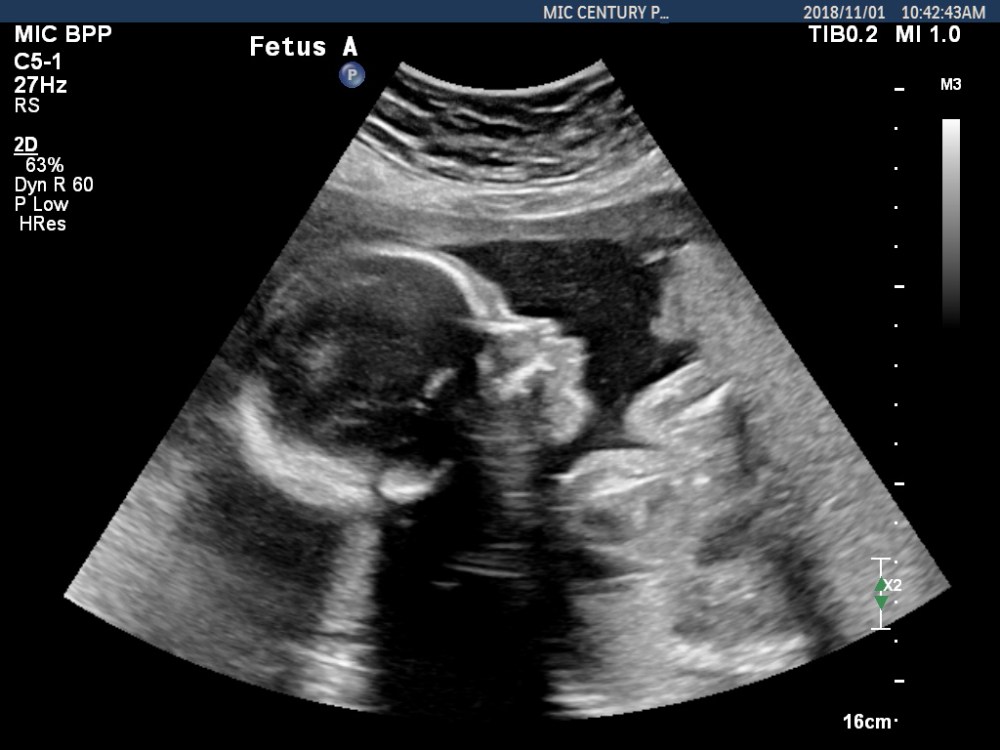

We have new baby photos! Auntie Pelican brought Alfalfa Sprout and Broccoli Sprout in for another ultrasound today to check their growth and all the other incredible processes that are unfolding as the date we meet our children approaches.

Check out these tiny people: